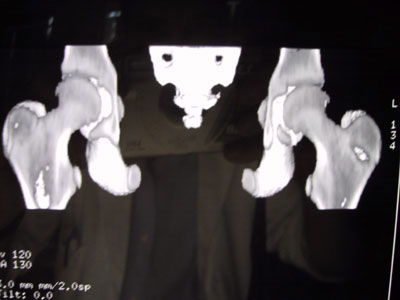

Alla TAC viene evidenziata una zona di lisi a livello del collo femorale in corrispondenza del gran trocantere.

Si segnala persistenza di ipotrofia muscolare alla coscia di sinistra. Si consiglia di eseguire scintigrafia ossea e di programmare biopsia. L'esame scintigrafico dello scheletro, eseguito dato il quesito clinico anche con tecnica trifasica e tomografica al bacino, evidenzia in fase osteotropa iperaccumulo del tracciante a gradiente piuttosto intenso in corrispondenza del gran trocantere del femore di sinistra, reperto che appare riconoscibile già nelle immagini precoci della fase dinamica e di pool ematico e che nelle immagini tomografiche interessa tutta la regione supero-laterale della porzione trocanterica del femore ed in parte il collo femorale, arrivando infero-lateralmente fin quasi al piccolo trocantere.